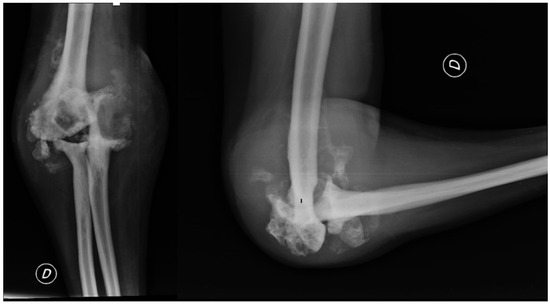

2.3. Further Investigations

2.2. Clinical Presentation